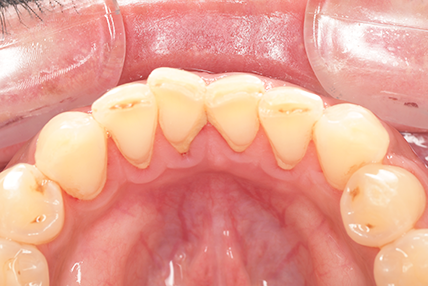

CASE 11

Before

After

基本情報

| 年齢・性別 | 32歳・男性 |

|---|---|

| 主訴 | 歯石をとりたい |

| 治療内容 | スケーリング |

| 治療期間 | 30分 |

| 治療費 | 1,500円(保険診療) |

| リスク・副作用 | 知覚過敏、歯肉退縮、出血 |

| 治療方針 | 今後も定期的にクリーニングを行っていきます。 |